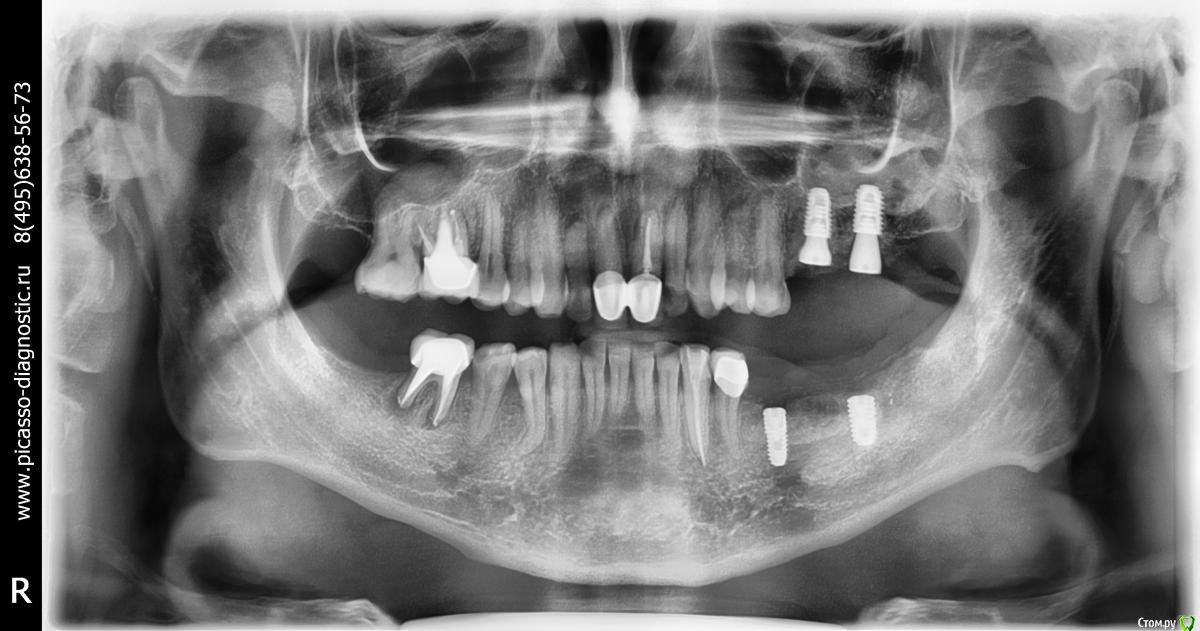

Большой Зеленый Опубликовано 9 октября, 2019 Поделиться Опубликовано 9 октября, 2019 , а операцию надо было закончить-так как и так 3 часа былаЕсть подозрение что Вы не в то место зашли. У меня на 4 имплантанта уходит максимум 30 минут. И то это если они в разных местах по разным челюстям. Снимки покажите Ссылка на комментарий

montus Опубликовано 9 октября, 2019 Автор Поделиться Опубликовано 9 октября, 2019 (изменено) Есть подозрение что Вы не в то место зашли. У меня на 4 имплантанта уходит максимум 30 минут. И то это если они в разных местах по разным челюстям. Снимки покажитена данный момент есть только такой снимок, остальные в клиникепроблема брака при установке была на нижней челюсти Изменено 9 октября, 2019 пользователем montus Ссылка на комментарий

Irouil Опубликовано 9 октября, 2019 Поделиться Опубликовано 9 октября, 2019 У осстемов винт, фиксирующий имплантоввод в имплантате может сломаться, если по ошибке взять не тот инструмент. Ключ там не похож на ключи в других системах, поэтому даже опытный, но первый раз работающий с этой системой доктор может ошибиться. Тогда, конечно, формирователь уже не закрутится. На снимке имплантаты выглядят установленными очень грамотно, поводов для беспокойств не вижу. Подмену имплантата исключаю. Проверяется это элементарно и проблем, в случае подмены, клиника наест себе на всю голову. Да и разница в стоимости между оригиналом и контрафактом будет априори мизерная. Ссылка на комментарий

Irouil Опубликовано 9 октября, 2019 Поделиться Опубликовано 9 октября, 2019 а верхнею то же так планирует мостом, если я не ошибаюсь. или там другие варианты по снимкуСудя по снимку там два имплантата рядом, поэтому каждый будет со своей коробкой, хотя их можно и объединить, но мостом они от этого не станут нагнал на меня страху, в пятницу первый остем инсталлирую )Ключ на имплантоввод просто накидной, слышал случаи как отвёрткой имплантат устанавливали и скручивали головку винта. Ссылка на комментарий